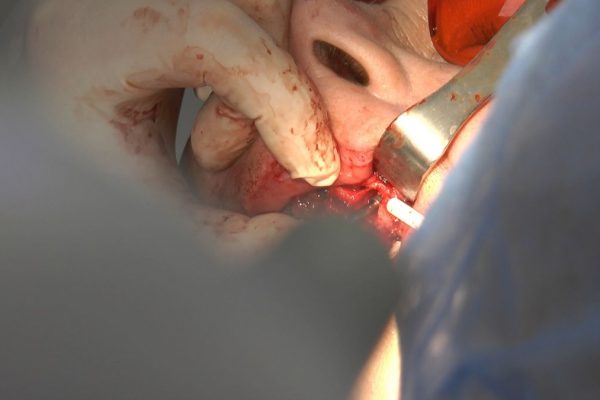

W ostatni weekend czerwca 2018 roku kursanci II Sezonu Preludium Implantologii odbyli piątą, finałową sesję, która w całości podporządkowana była praktyce. W ciągu dwóch dni zabiegowych Lekarze uczestniczący w szkoleniu przeprowadzili szereg zabiegów pod kierunkiem dr n.med. Violetty Szycik. Wszczepili 17 implantów oraz przeprowadzili ekstrakcje i zabiegi regeneracyjne kości. Zabiegi były wykonywane także w sedacji dożylnej z udziałem specjalisty anestezjologii i intensywnej terapii dr Jolanty Grzybowskiej. Preludium implantologii to nowy program edukacyjny dla adeptów implantologii stomatologicznej, którego celem jest wprowadzenie do implantologii poprzez pozyskanie wiedzy w szerokim zakresie i uwzględnieniem szczegółów mających decydujące znaczenie dla powodzenia leczenia implantologicznego. Ale tak jak wszystkie szkolenia w Instytucie Vivadental, w tym wiodące Practiculum Implantologii, zorientowane jest na praktyce i samodzielnym wykonywaniu zabiegów pod kierunkiem Mentora. To najlepsza edukacja w medycynie zabiegowej, a zarazem najlepszy start do implantologii.